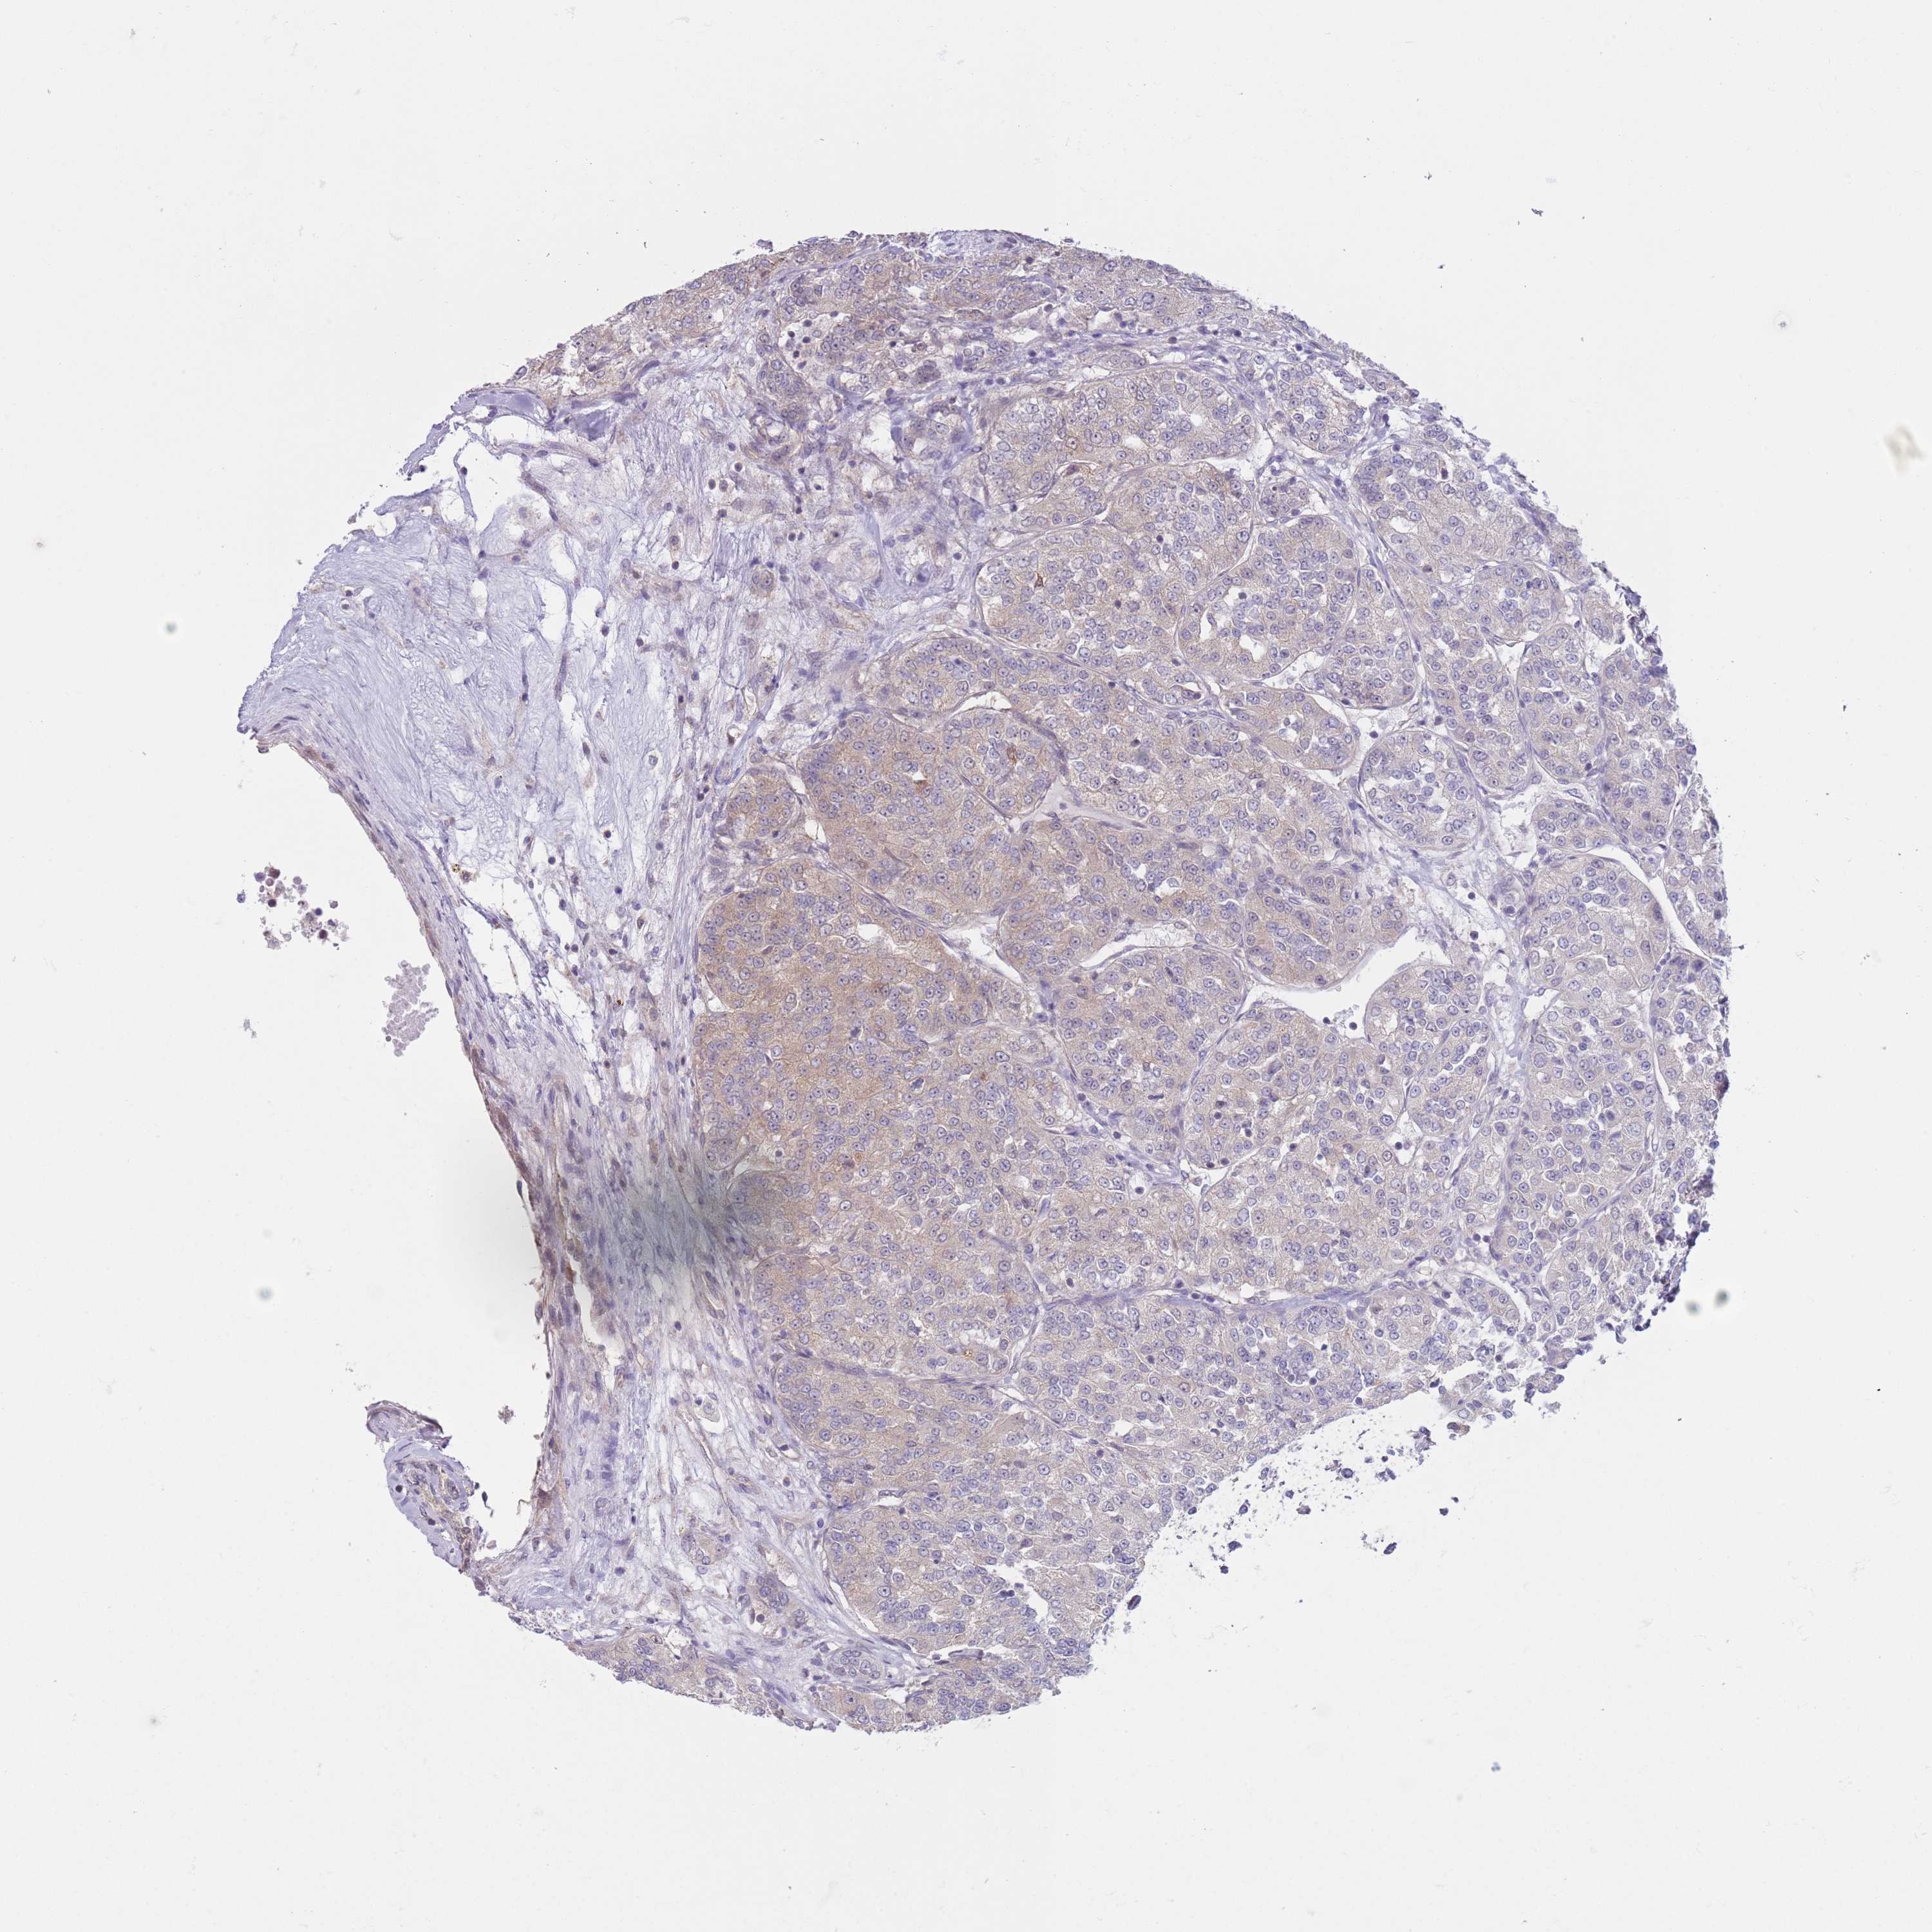

KIDNEY RENAL CLEAR CELL CARCINOMA (VALIDATION) - Interactive survival scatter ploti

The Survival Scatter plot shows the clinical status (i.e. dead or alive) for all individuals in the patient cohort, based on the same data that underlies the corresponding Kaplan-Meier plots. Patients that are alive at last time for follow-up are shown in blue and patients who have died during the study are shown in red.

The x-axis shows the expression levels (FPKM) of the investigated gene in the tumor tissue at the time of diagnosis. The y-axis shows the follow-up time after diagnosis (years). Both axes are complimented with kernel density curves demonstrating the data density over the axes. The top density plot shows the expression levels (FPKM) distribution among dead (red) and alive patients (blue). The right density plot shows the data density of the survived years of dead patients with high and low expression levels respectively, stratified using the cutoff indicated by the vertical dashed line through the Survival Scatter plot. This cutoff is automatically defined based on the FPKM cutoff that minimizes the p-score. The cutoff can be changed by dragging the vertical line or by entering a cutoff value in the square labeled "Current cut-off".

Under the Survival Scatter plot the p-score landscape (black curve; left axis) is shown together with dead median separation (red curve; right axis). Dead median separation is the difference in median mRNA expression between patients who have died with high and low expression, respectively. It is calculated as follows: median FPKM expression of dead patients with high expression - median FPKM expression of dead patients with low expression. This is intended to aid the user in visually exploring custom cutoffs and the associated p-scores and dead median separation.

Individual patient data is displayed and can be filtered by clicking on one or more of the category buttons on the top of the page. Categories describing expression level and patient information include: high, low, alive, dead, female, male and tumor stages. The scale of the x-axis can be toggled between linear and log-scale by clicking on the "x log" button. Mouse-over function shows TCGA ID, patient information and mRNA expression (FPKM) for each patient.

& Survival analysisi

Kaplan-Meier plots summarize results from analysis of correlation between mRNA expression level and patient survival. Patients were divided based on level of expression into one of the two groups "low" (under cut off) or "high" (over cut off). X-axis shows time for survival (years) and y-axis shows the probability of survival, where 1.0 corresponds to 100 percent.

COPE is not prognostic in Kidney Renal Clear Cell Carcinoma (validation)

Best expression cut offi

Based on the FPKM value of each gene, patients were classified into two groups and association between prognosis (survival) and gene expression (FPKM) was examined. The best expression cut-off refers the FPKM value that yields maximal difference with regard to survival between the two groups at the lowest log-rank P-value. Best expression cut-off was selected based on survival analysis .

When clicking on this number, the vertical dashed line indicating cut-off, the interactive survival plot, and the Kaplan-Meier curve will be adjusted to show results based on the best expression cut-off.

: 122.91

TCGA RNA samplesi

RNA-seq data is reported as average FPKM (number Fragments Per Kilobase of exon per Million reads), generated by the The Cancer Genome Atlas (TCGA) .

Normal distribution across the dataset is visualized with box plots, shown as median and 25th and 75th percentiles. Points are displayed as outliers if they are above or below 1.5 times the interquartile range. FPKM values of the individual samples are presented next to the box plot.

Average pTPM 135.1

Number of samples 100